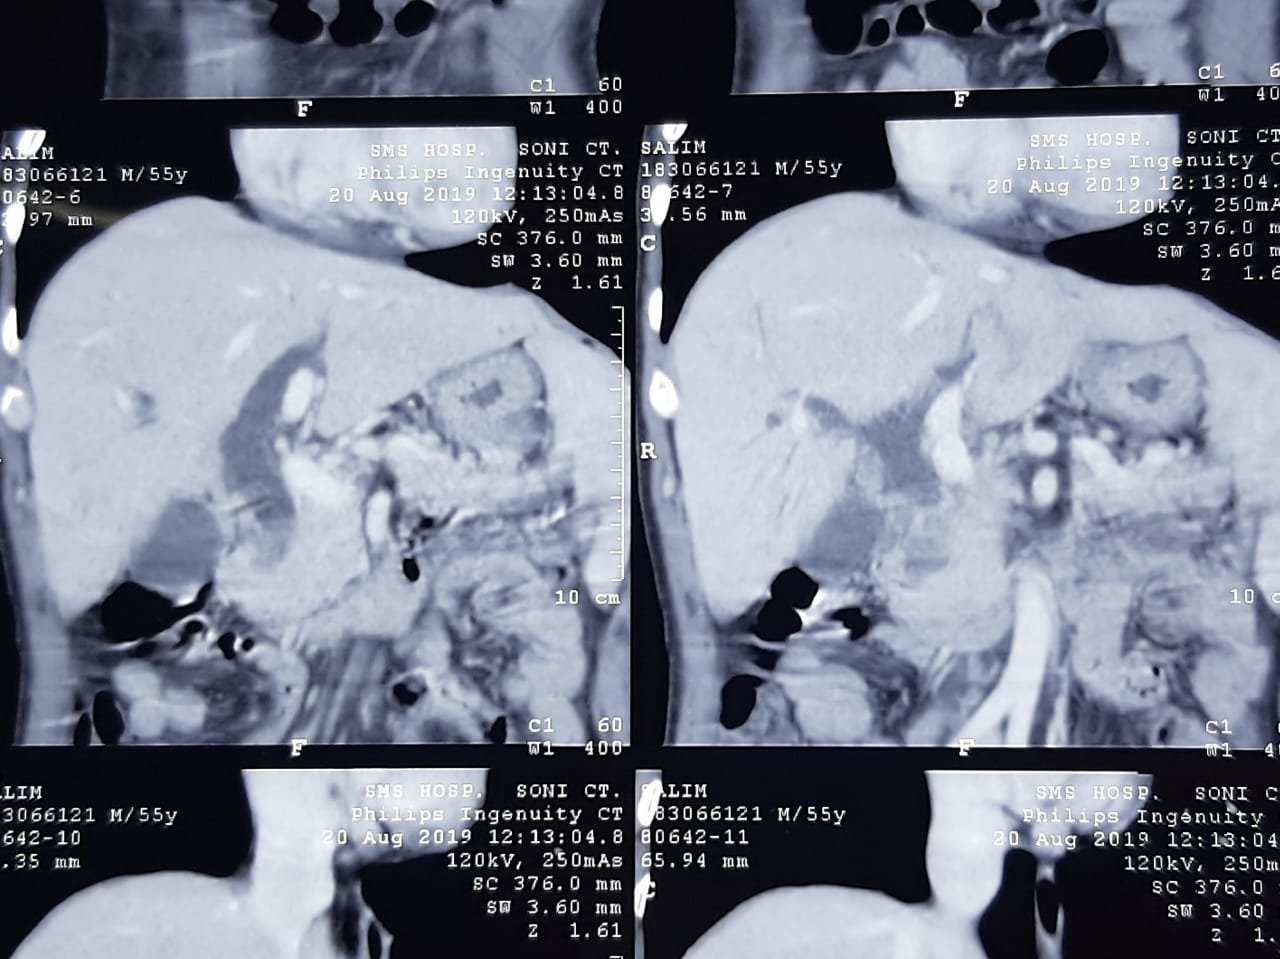

Multidetector thin slice CT scan is helpful both in diagnosis, staging of disease and in treatment planning.

CT Scan of above patient (60 year old male) showing cancer in pancreas which can be resected by surgery.